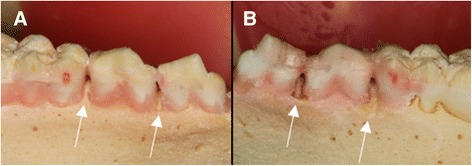

The same researcher (VCA) who performed soft tissue simulation produced bone lesions. A cotton pellet was placed at the interproximal space, filling all the available space, an then soaked with perchloric acid 70–72% [20, 26] using a disposable syringe, until it was visible fulfilled. Cotton pellets were left in contact with bone for 1 h and replaced every hour until experimental times of 2, 4 or 6 h were achieved in order to produce standardized bone lesions with sizes varying from small to large. Figure 2a depicts a control site between first molar and second premolar and a two-hour lesion between first and second premolar. Figure 2b presents a six-hour lesion between first and second premolar and a four-hour lesion between second premolar and first molar. Once the experimental time was achieved, the site was washed and dried.

Fig. 2.

Swine mandibles with bone lesions. a. No lesion (control) between first molar and second premolar. Two-hour lesion between first and second premolar. b. Six-hour lesion between first and second premolar. Four-hour lesion between second premolar and first molar